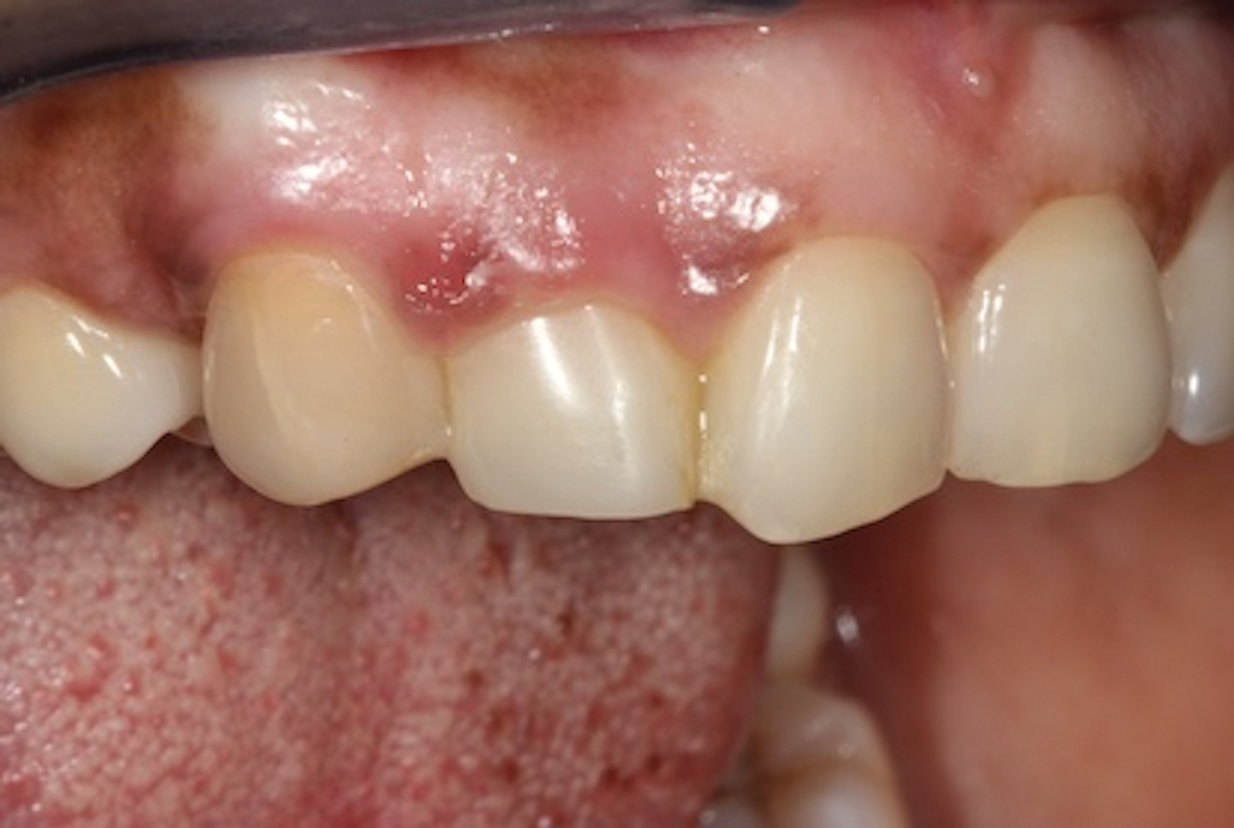

Depending on whether patients present with an existing edentulous space or a non-restorable tooth requiring extraction, as well as other factors, their long-term treatment goals may vary. Nonetheless, each case should be evaluated to identify patients' needs regarding immediate restoration. In the example case presented here, a radiographic examination of a discolored canine lead to the discovery of a lateral incisor (tooth No. 7) with internal resorption that required extraction (Figure 1). The tooth was extracted, and an implant was subsequently placed (Figure 2); however, the patient would be unable to complete the treatment for an extended period of time, so a fiber-reinforced composite bridge was chosen to serve as an ideal long-term provisional replacement option.

(2.) Close-up right lateral view of the tooth No. 7 site following extraction and implant placement.

Figure 2